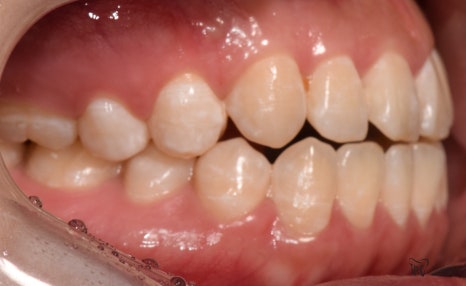

구강 내 사진을 보면, 전형적인 Open bite 의

형태를 띄고 있는 것을 보실 수 있습니다.

그 정도는, 그렇게 심하지는 않으나

치아교정 을 받지 않는다면 턱관절 에

더 큰 문제를 일으킨다는 것을 본인 스스로도

잘 알고 있었기 때문에 저에게 진료를

의뢰했었습니다.